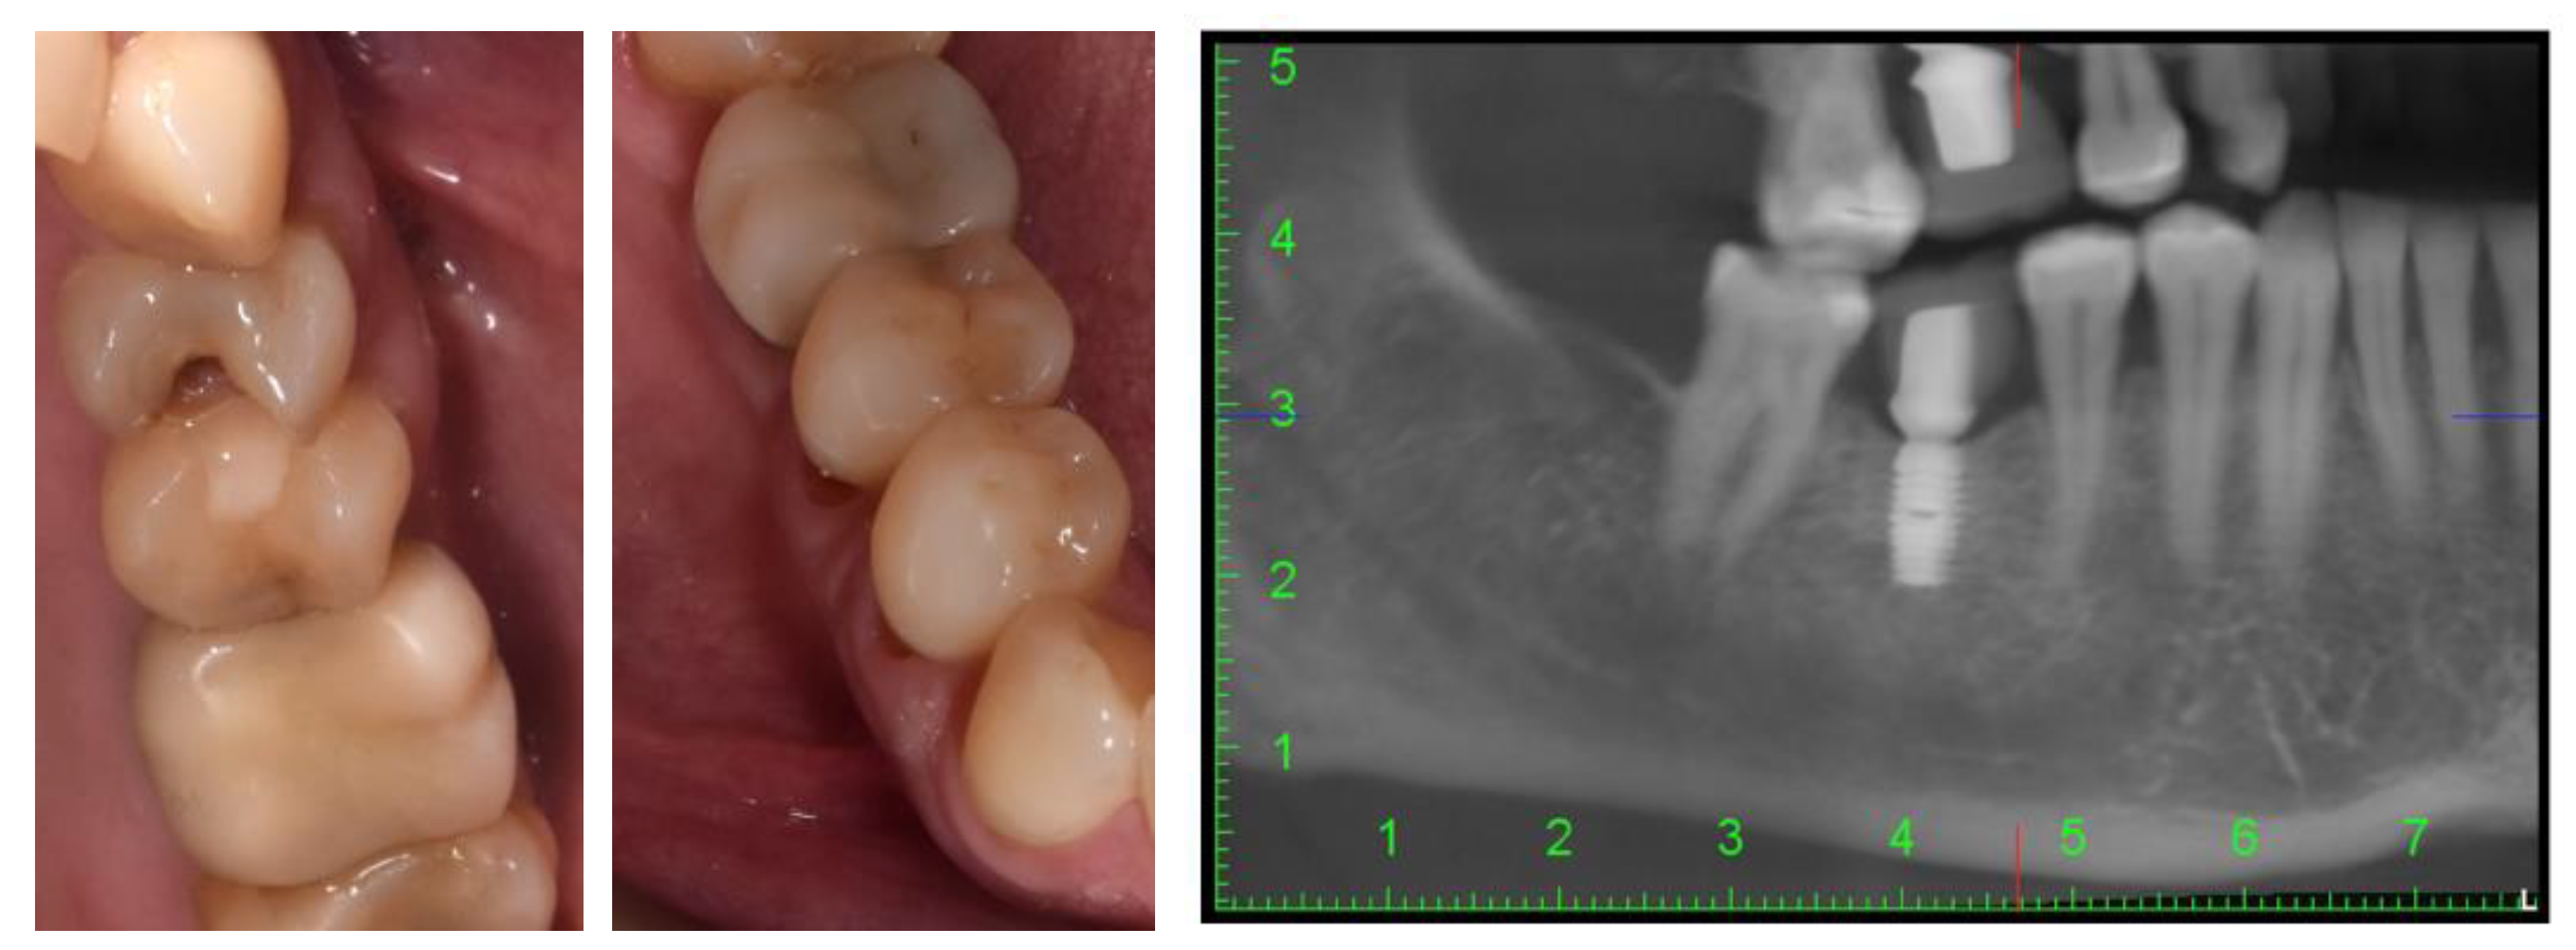

2. Case Description